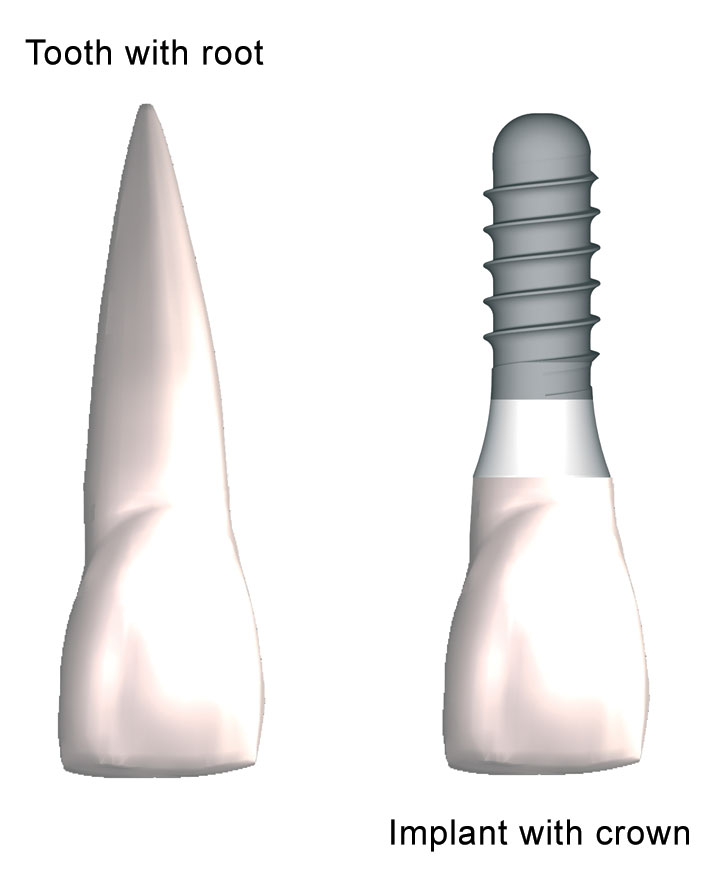

¿Qué es un implante?

Los implantes dentales son dispositivos que, insertados en el hueso, funcionan o actúan como una raíz artificial, soportando así la futura corona protética por medio de un aditamento intermedio conocido como pilar.

La sustitución con éxito de los dientes naturales perdidos por análogos de las raíces dentarias, los implantes, constituye uno de los mayores avances clínicos en los tratamiento odontológicos. Esta modalidad de tratamiento estará condicionada a las características de cada paciente, siendo la disponibilidad ósea el factor clave para poder llevar a cabo.